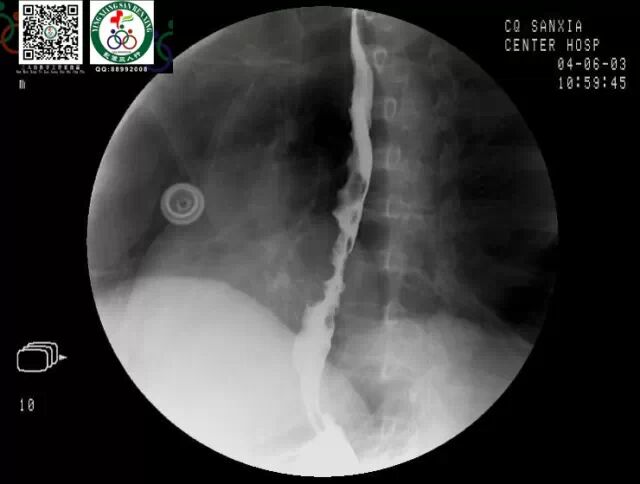

上消化道钡餐(同一病人,几个病典型征象有出现啦)